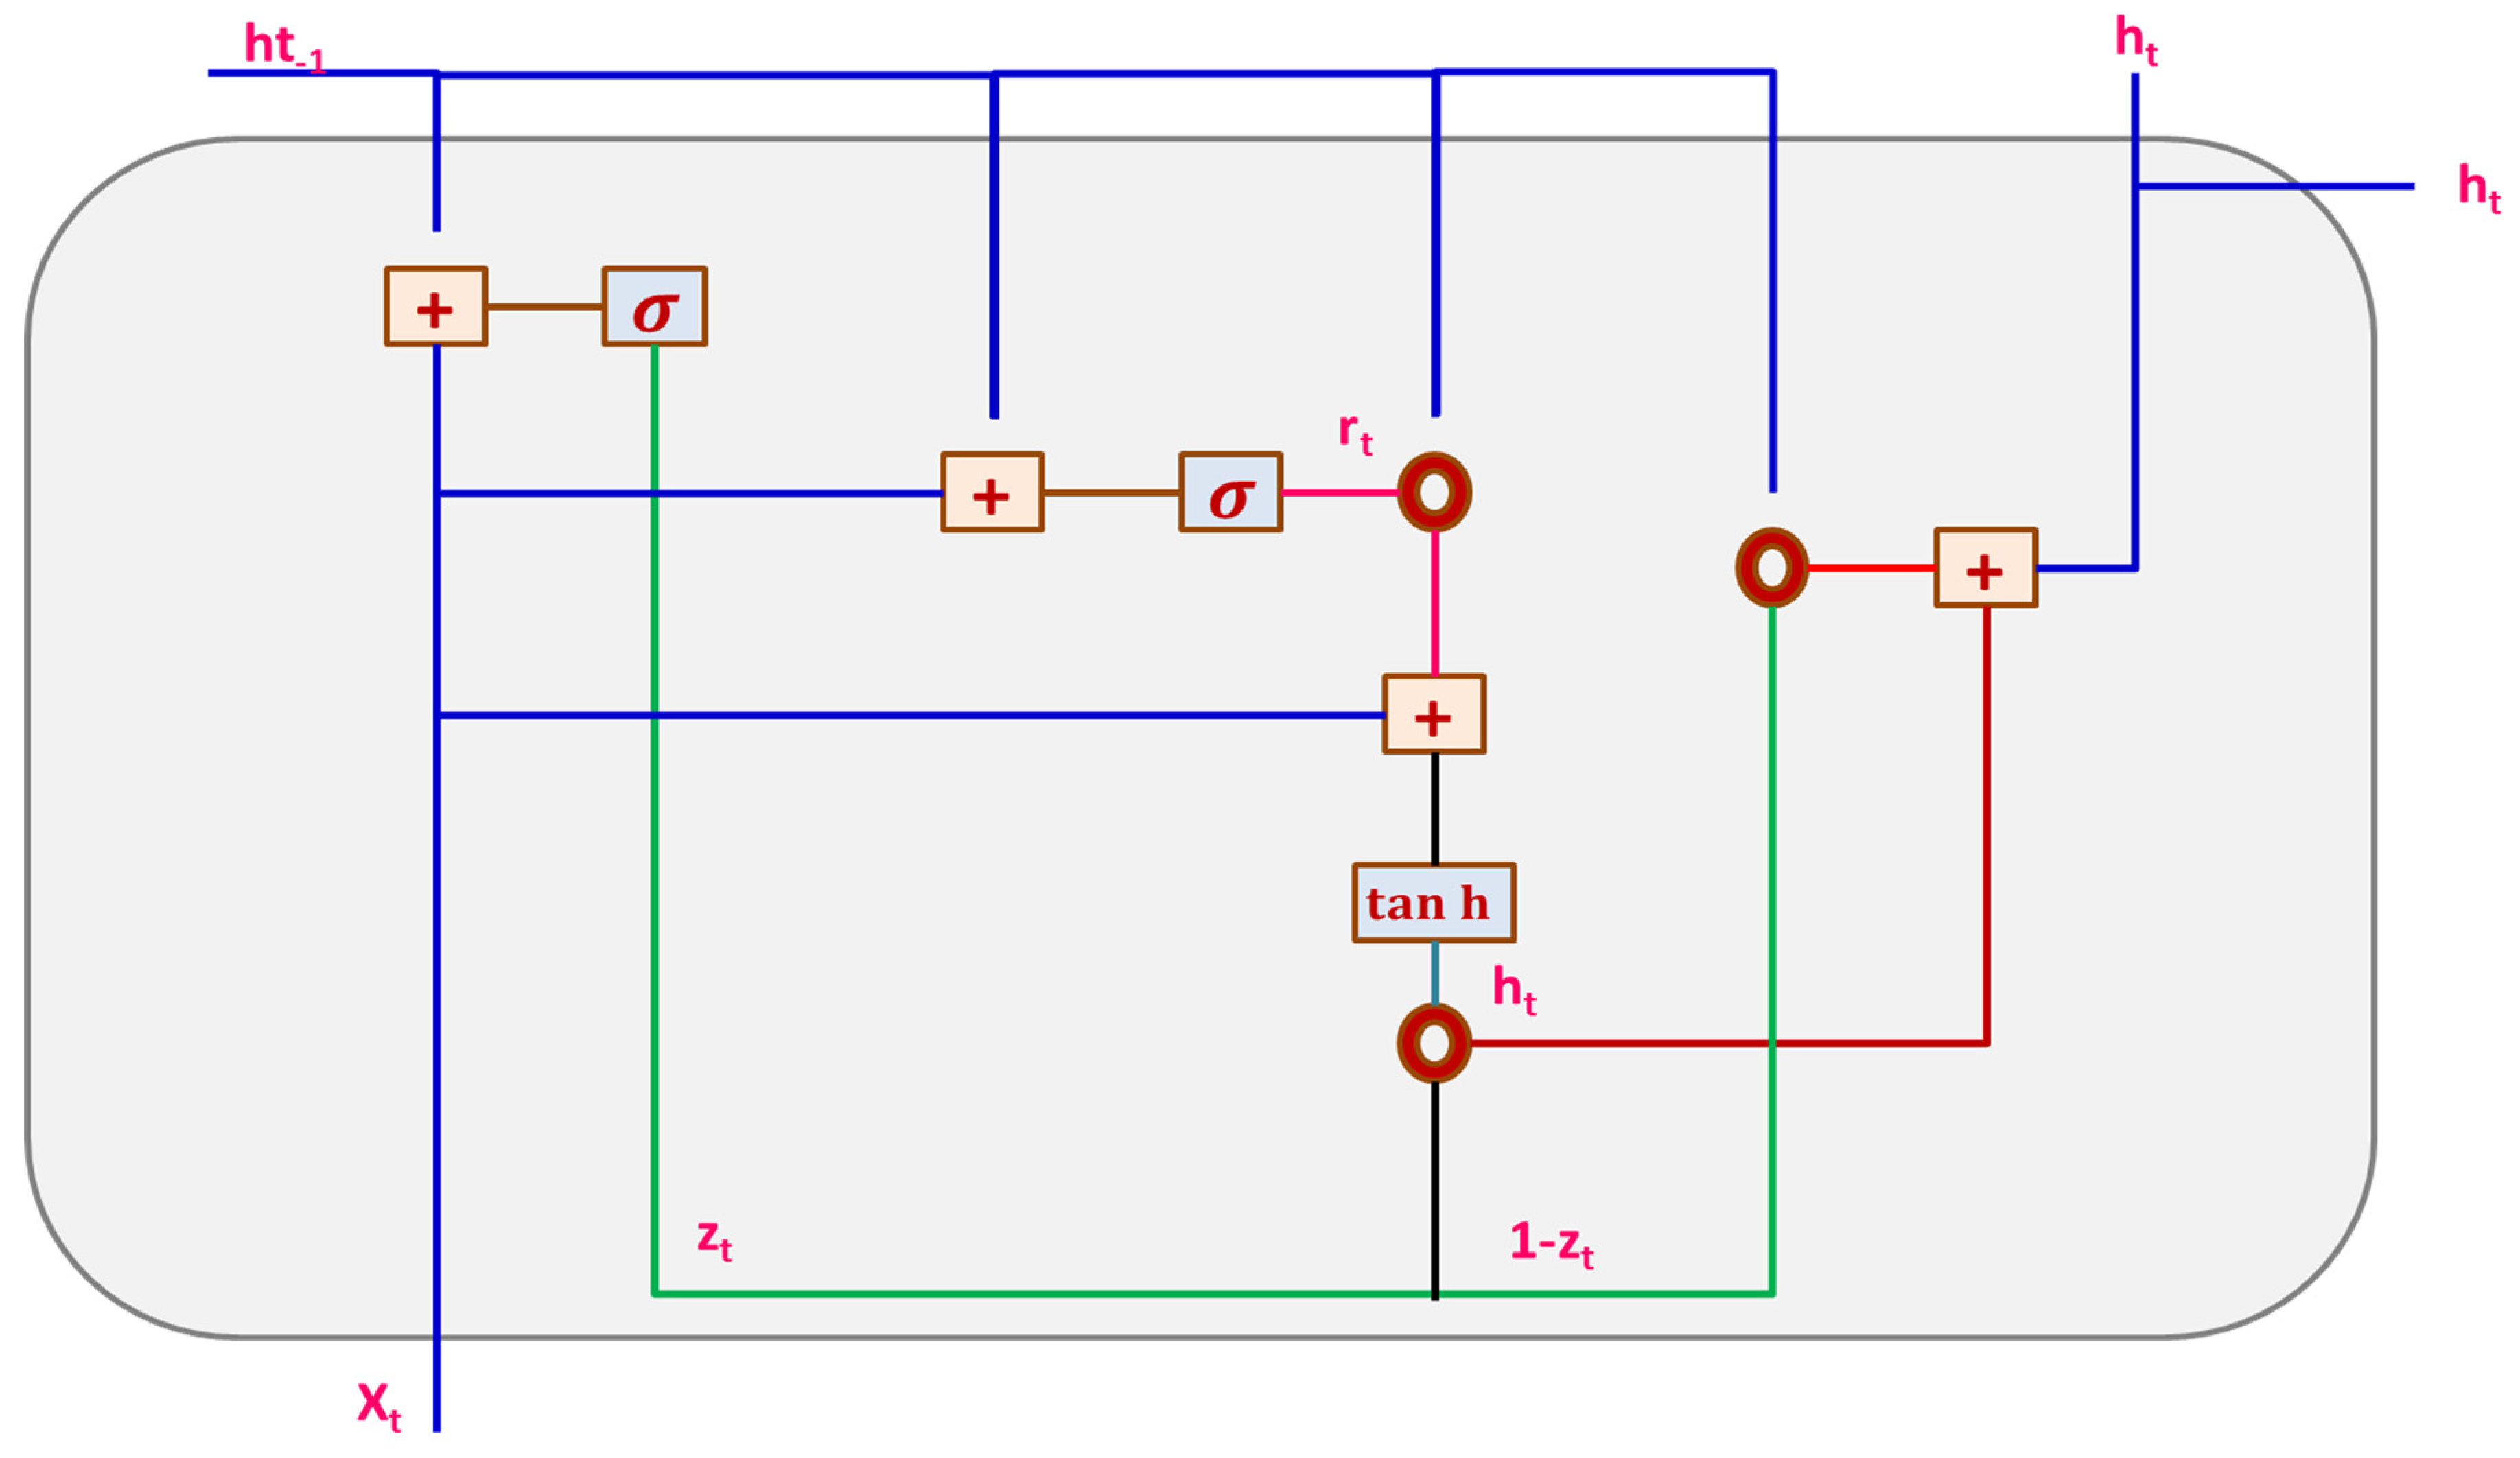

3.3.2. Gated Recurrent Unit Network (GRU)

3.3.3. CNN-GRU